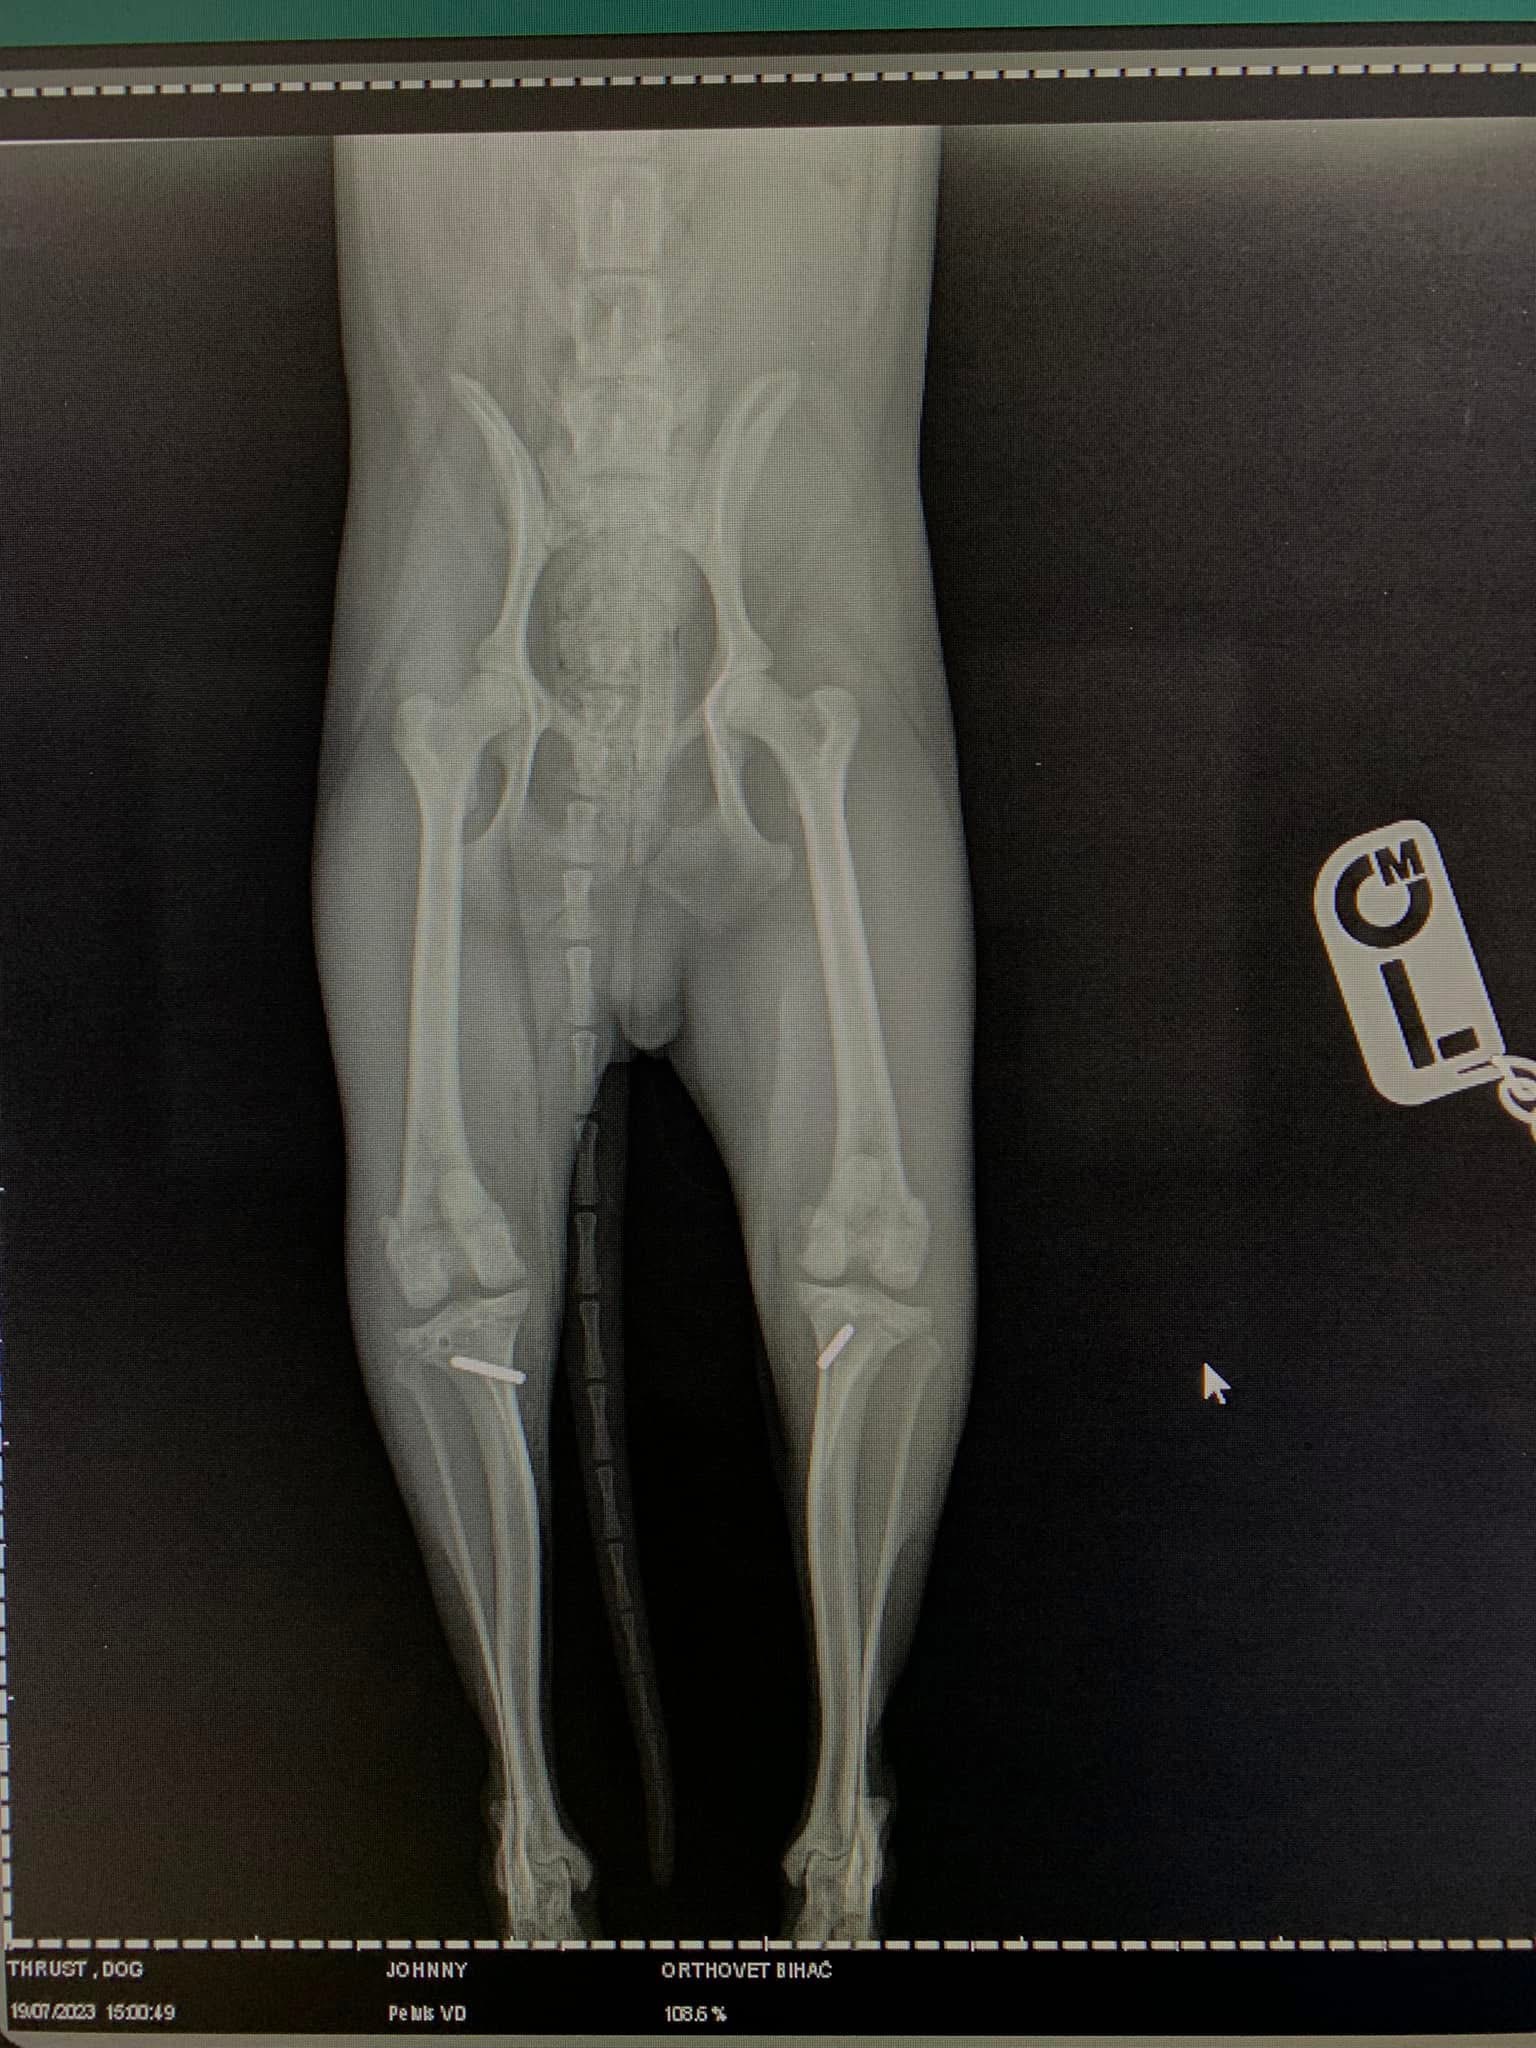

- Liječenje prijeloma kostiju, uključujući intraartikularne frakture

- Liječenje luksacije patele(Luxatio Patellae) Trohleoplastika i TTT(eng. Tibial Tuberosity Transposition)

- Korektivne osteotomije za ispravljanje deformiteta

- Liječenje rupture prednjeg križnog ligamenta koljena TPLO (eng. Tibial Plateau Leveling Osteotomy)